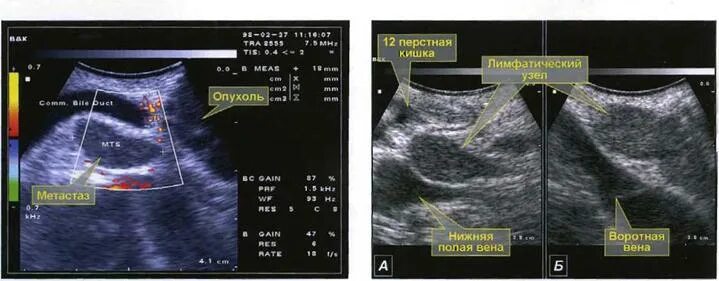

Метастазы в лимфоузлах форум